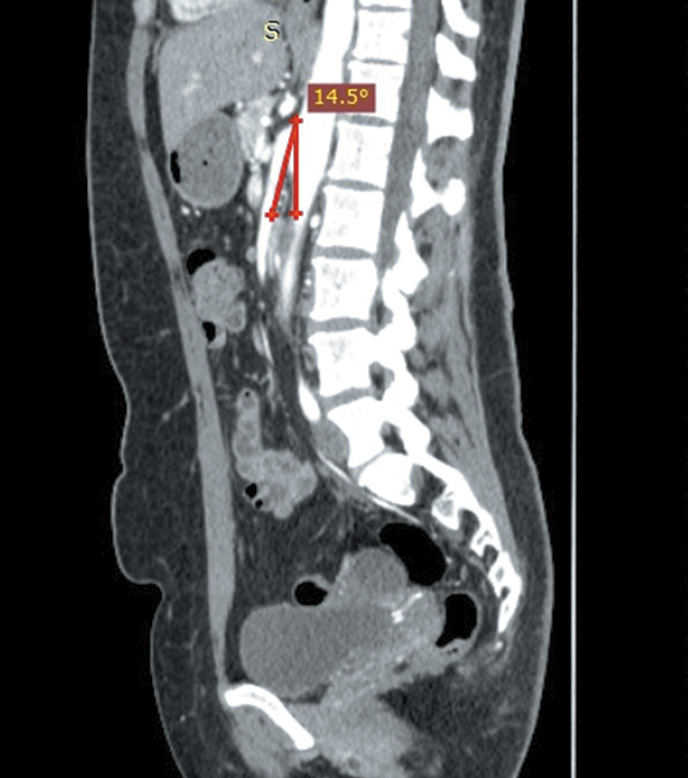

18.09.2019 выполнена контрольная спиральная компьютерная томографическая ангиография, по данным которой верхняя брыжеечная артерия длиной 5 мм отходит от аорты под острым углом (14,5°) (рис. 2).

Рис. 2. Компьютерная томограмма органов брюшной полости с контрастированием (маркирован угол отхождения верхней брыжеечной артерии от аорты)

Fig. 2. CT-picture of abdominal organs with contrast (the angle of superior mesenteric artery discharge from the aorta is shown)